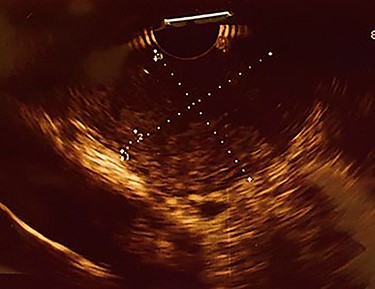

Upper gastrointestinal endoscopic examination revealed a polypoid submucosal lesion in the first part of the duodenum (Fig. 2a and b). The mass was freely mobile, intermittently projected, moving back and forth through the pylorus causing intermittent obstruction. Endoscopic ultrasound revealed hypoechoic submucosal lesion measuring 2.9 × 2.8 cm (Fig. 3).

Endoscopic ultrasound, showing heterogeneous hypoechoic subepithelial lesion.